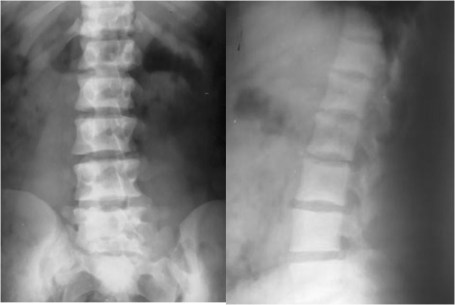

SIGNO DE LA C

Signo de coalición subtalar (fusión calcáneo-astragalina) en la radiografía lateral del tobillo. La «C» se forma por el límite medial de la cúpula talar y el límite posteroinferior del sustentaculum tali.

En la radiografía lateral de tobillo hemos marcado con flechas la «C» que da nombre al signo.

La fusión calcáneo-astragalina (flecha) se comprueba en el corte coronal de TC de tobillo.

Referencia: Lateur LM y cols. Subtalar coalition: diagnosis with the C sign on lateral radiographs of the ankle. Radiology 1994; 193: 847-851.